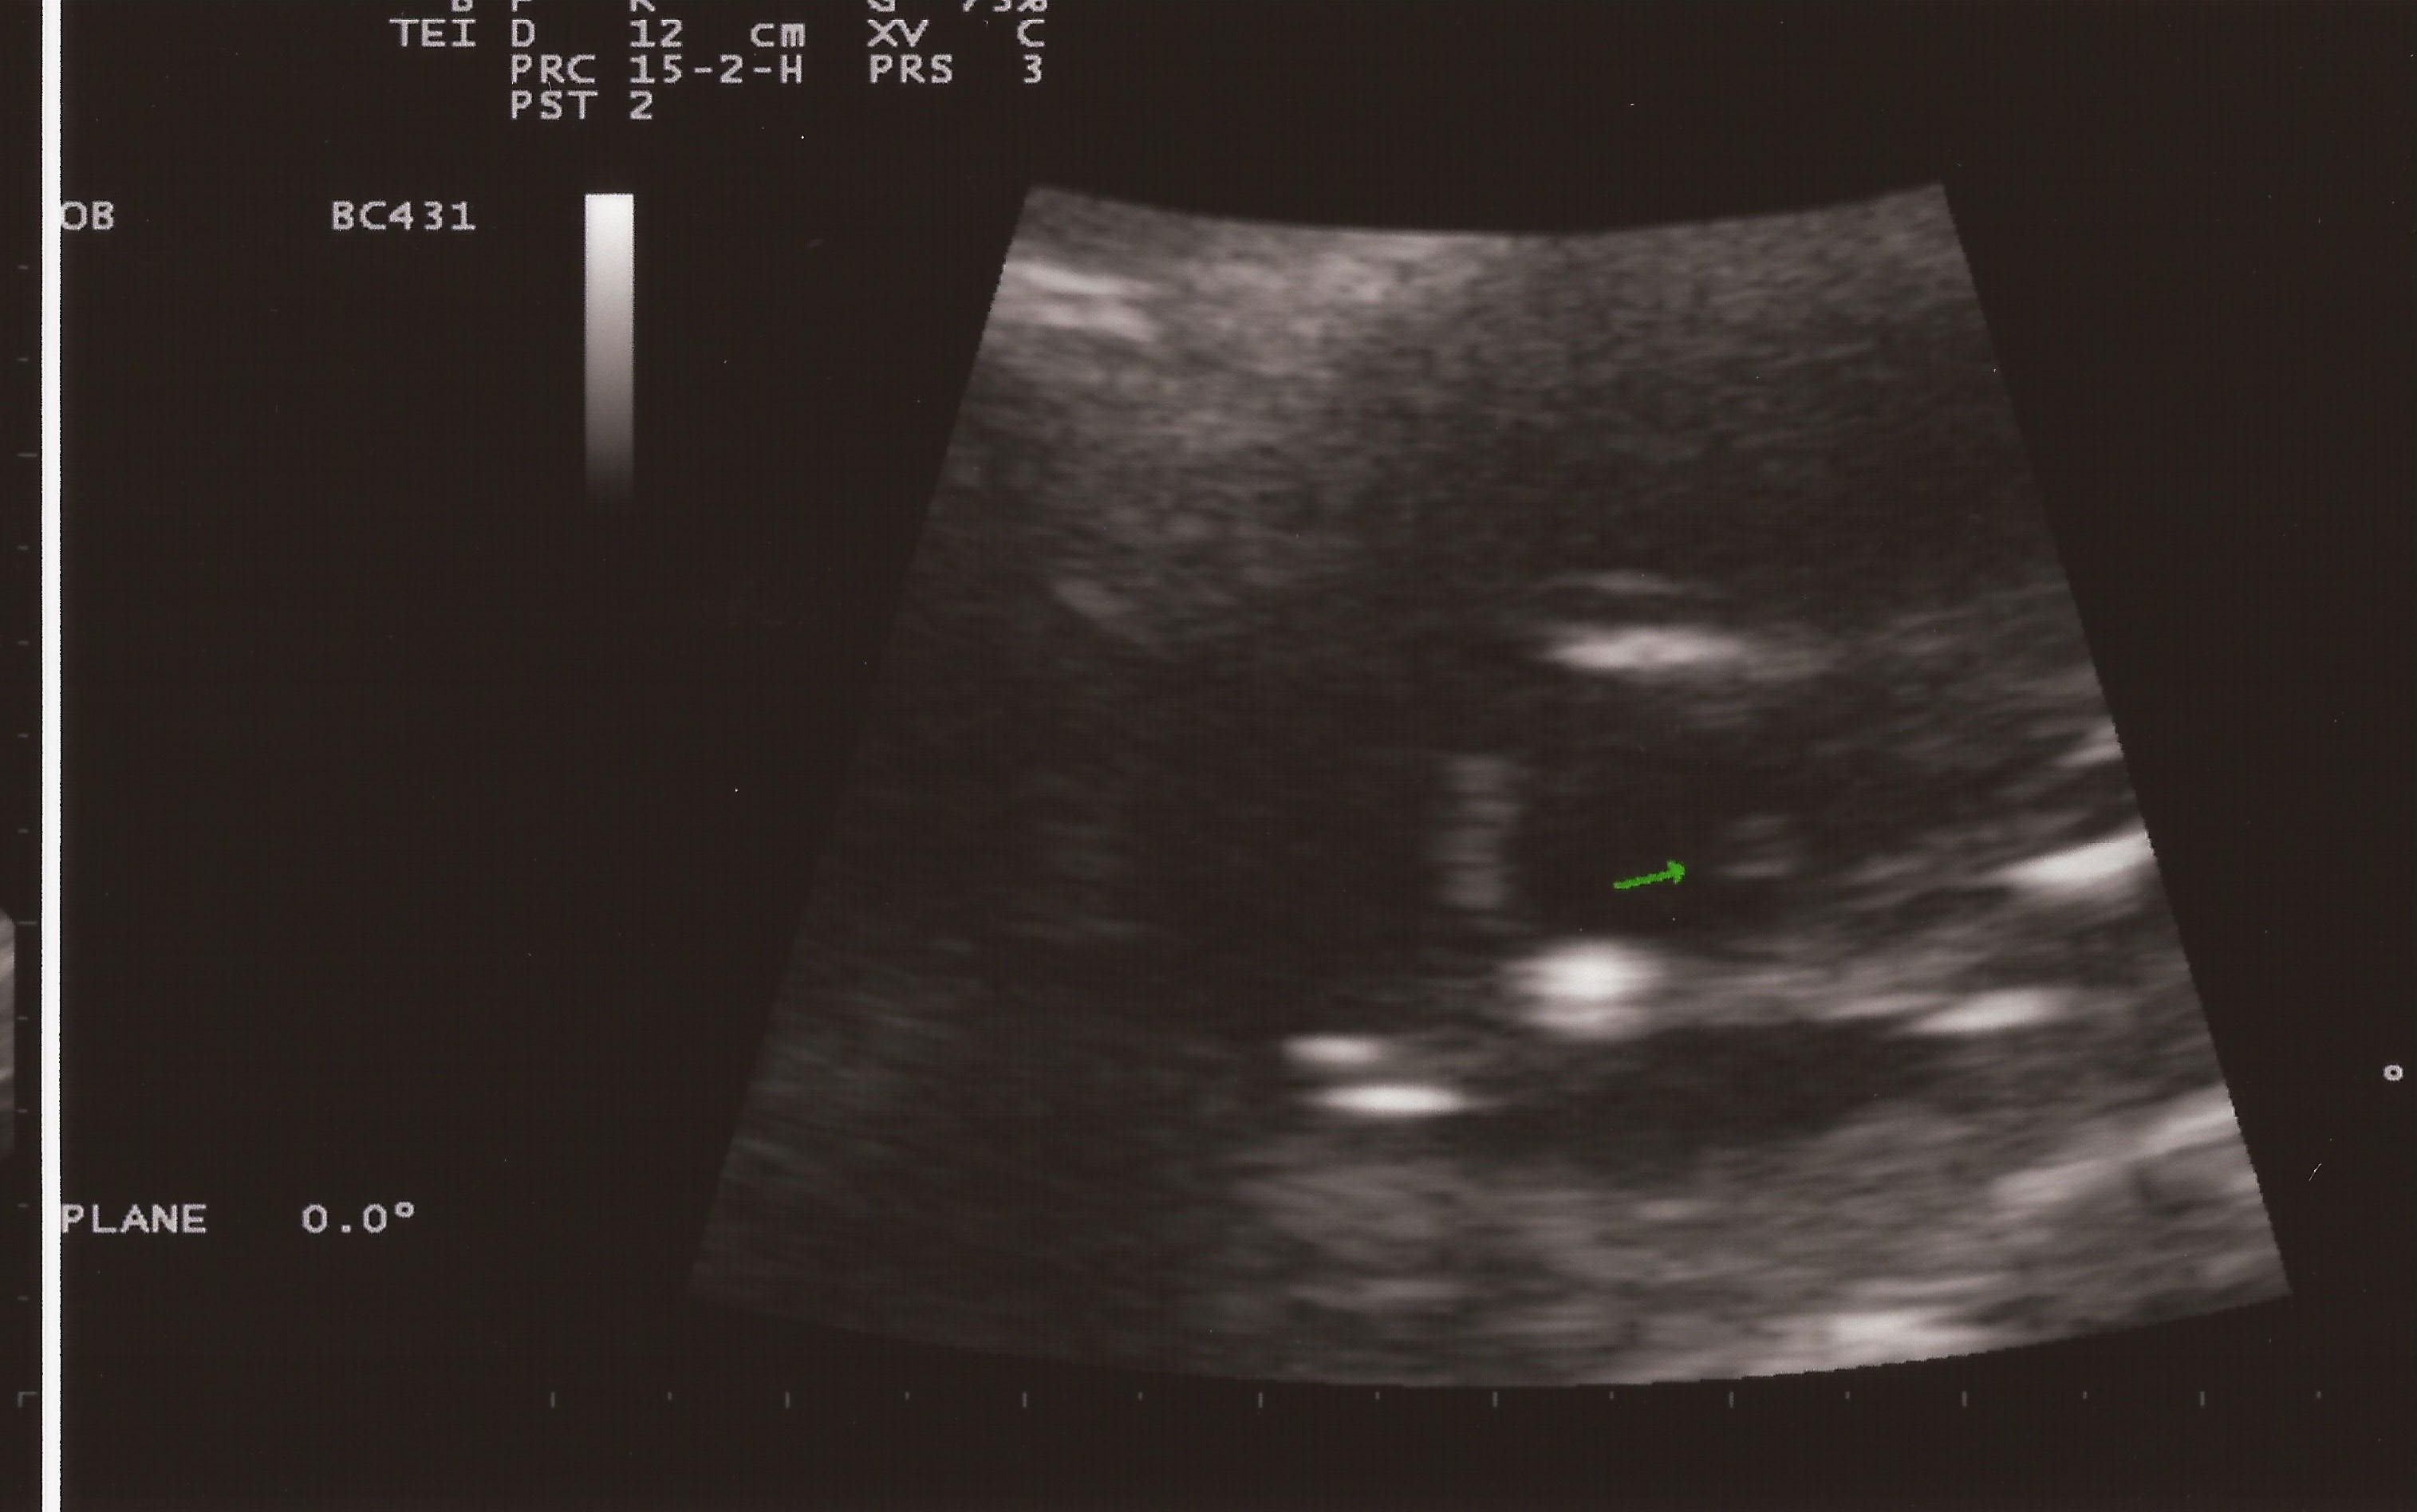

Attachment 5658Attachment 5657

So I am going next week for an actual gender check ultrasound but today the tech went poking around to see what she could find. Well she found confusion... one pic looks girly and one looks possibly boy (she did say it could be umbilical cord) - she wouldn't give me an opinion. What is yours?